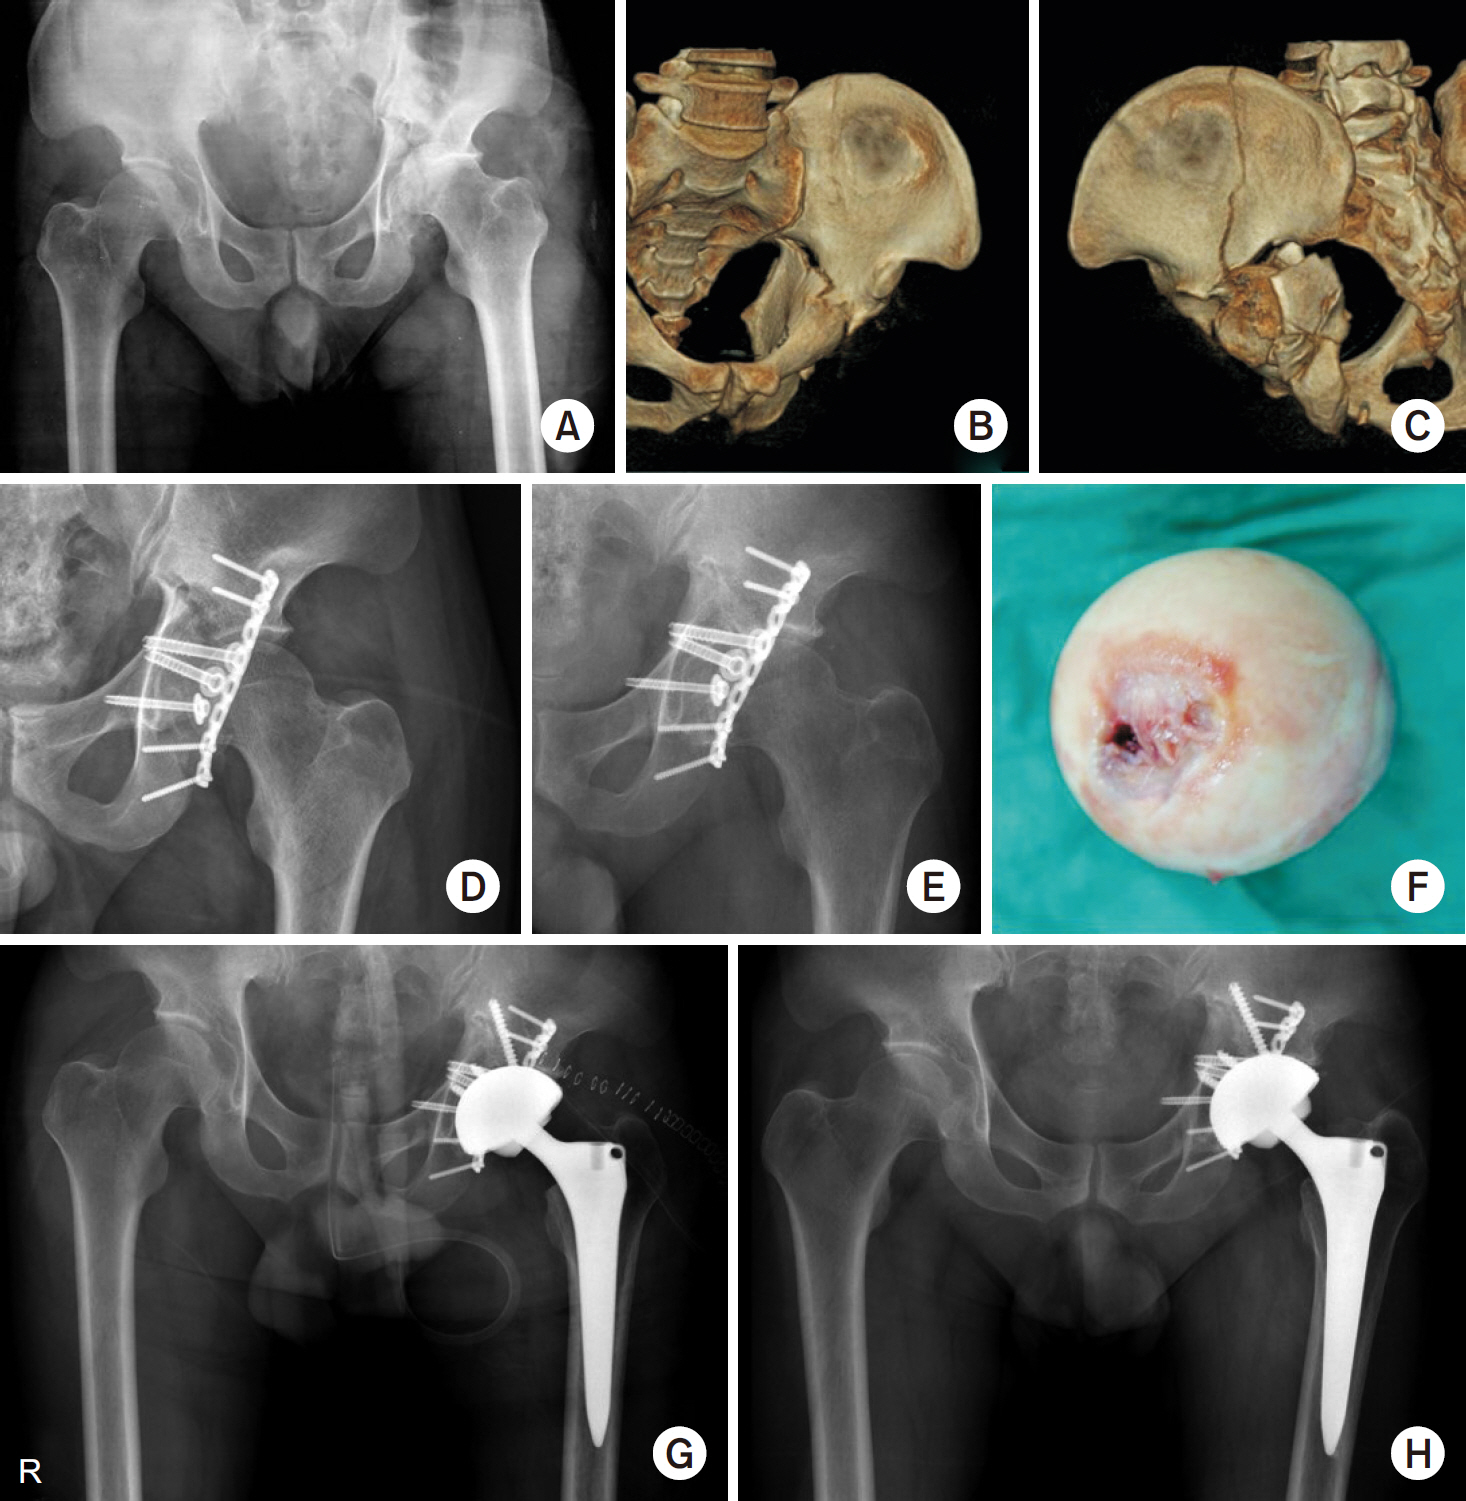

Fig. 2.

(A) Preoperative anteroposterior radiograph of a 67-year-old male showed a transverse fracture with posterior wall fracture of the acetabulum and severe impaction. (B, C) Computed tomography showed a severe comminuted fracture of the posterior wall and protrusion of the femoral head. (D) The acetabular mesh plate was inserted into the acetabulum through the Kocher–Langenbeck approach. (E) Autogenous corticocancellous bone from the femoral head was grafted on a mesh plate to support the acetabular cup. (F) A liner was inserted after fixation of the cemented flanged acetabular cup. (G) Postoperative anteroposterior radiograph after internal fixation and total hip arthroplasty. (H) Three-year postoperative radiographs showed stable total hip arthroplasty.